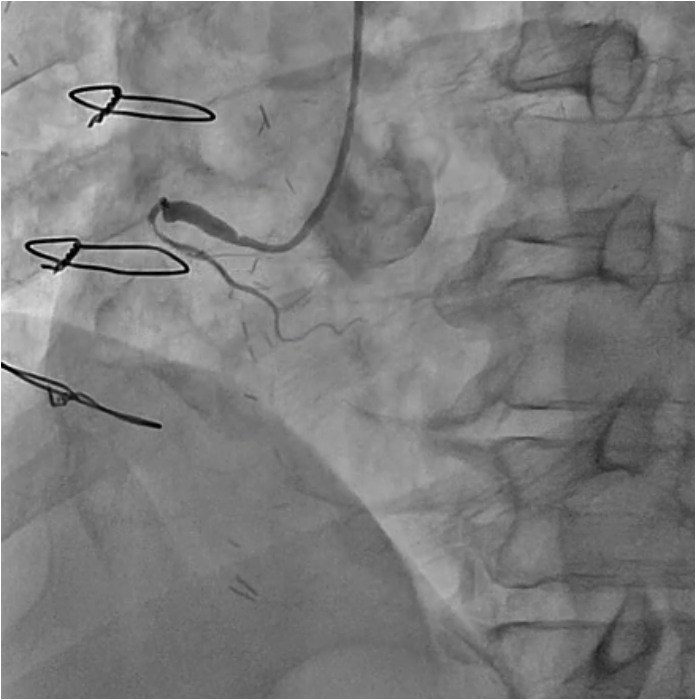

PCI for the degenerated SVG was determined to be at high risk of distal embolism so we planned to perform PCI for native RCA. Antegrade wire crossing was thought to be difficult (J-CTO score was 3 : calcification, bending and lesion length), therefore we planned retrograde approach via SVG. To avoid ischemia during the retrograde procedure, we dilated the severe stenotic lesion in SVG with small balloon and then micro catheter was advanced. It was very difficult to pass the graft anastomosis, but reverse wire technique at distal RCA was effective. Even after the advancement of both antegrade and retrograde wires, it was also difficult to pass the CTO lesion due to strong bending. Finally, retrograde wire was passed with Reverse CART technique and externalization was achieved. After DES implantation, native RCA was nicely revascularized.

Case Summary